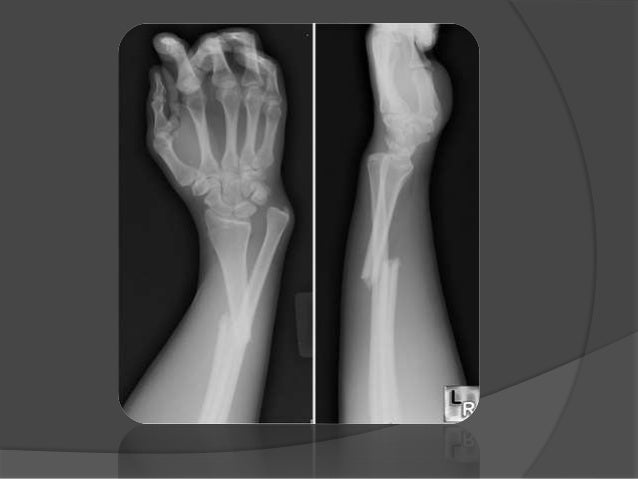

Fractura De La Diáfisis Del Cúbito Y Del Radio

Una fractura de la diáfisis del cúbito y del radio significa que ambos huesos largos del antebrazo (cúbito y radio) están rotos en su parte media, llamada diáfisis. Es una lesión común, especialmente en niños y adultos jóvenes.

El diagnóstico generalmente se realiza mediante un examen físico realizado por un médico y radiografías (rayos X). Las radiografías mostrarán la ubicación y el tipo de fractura.